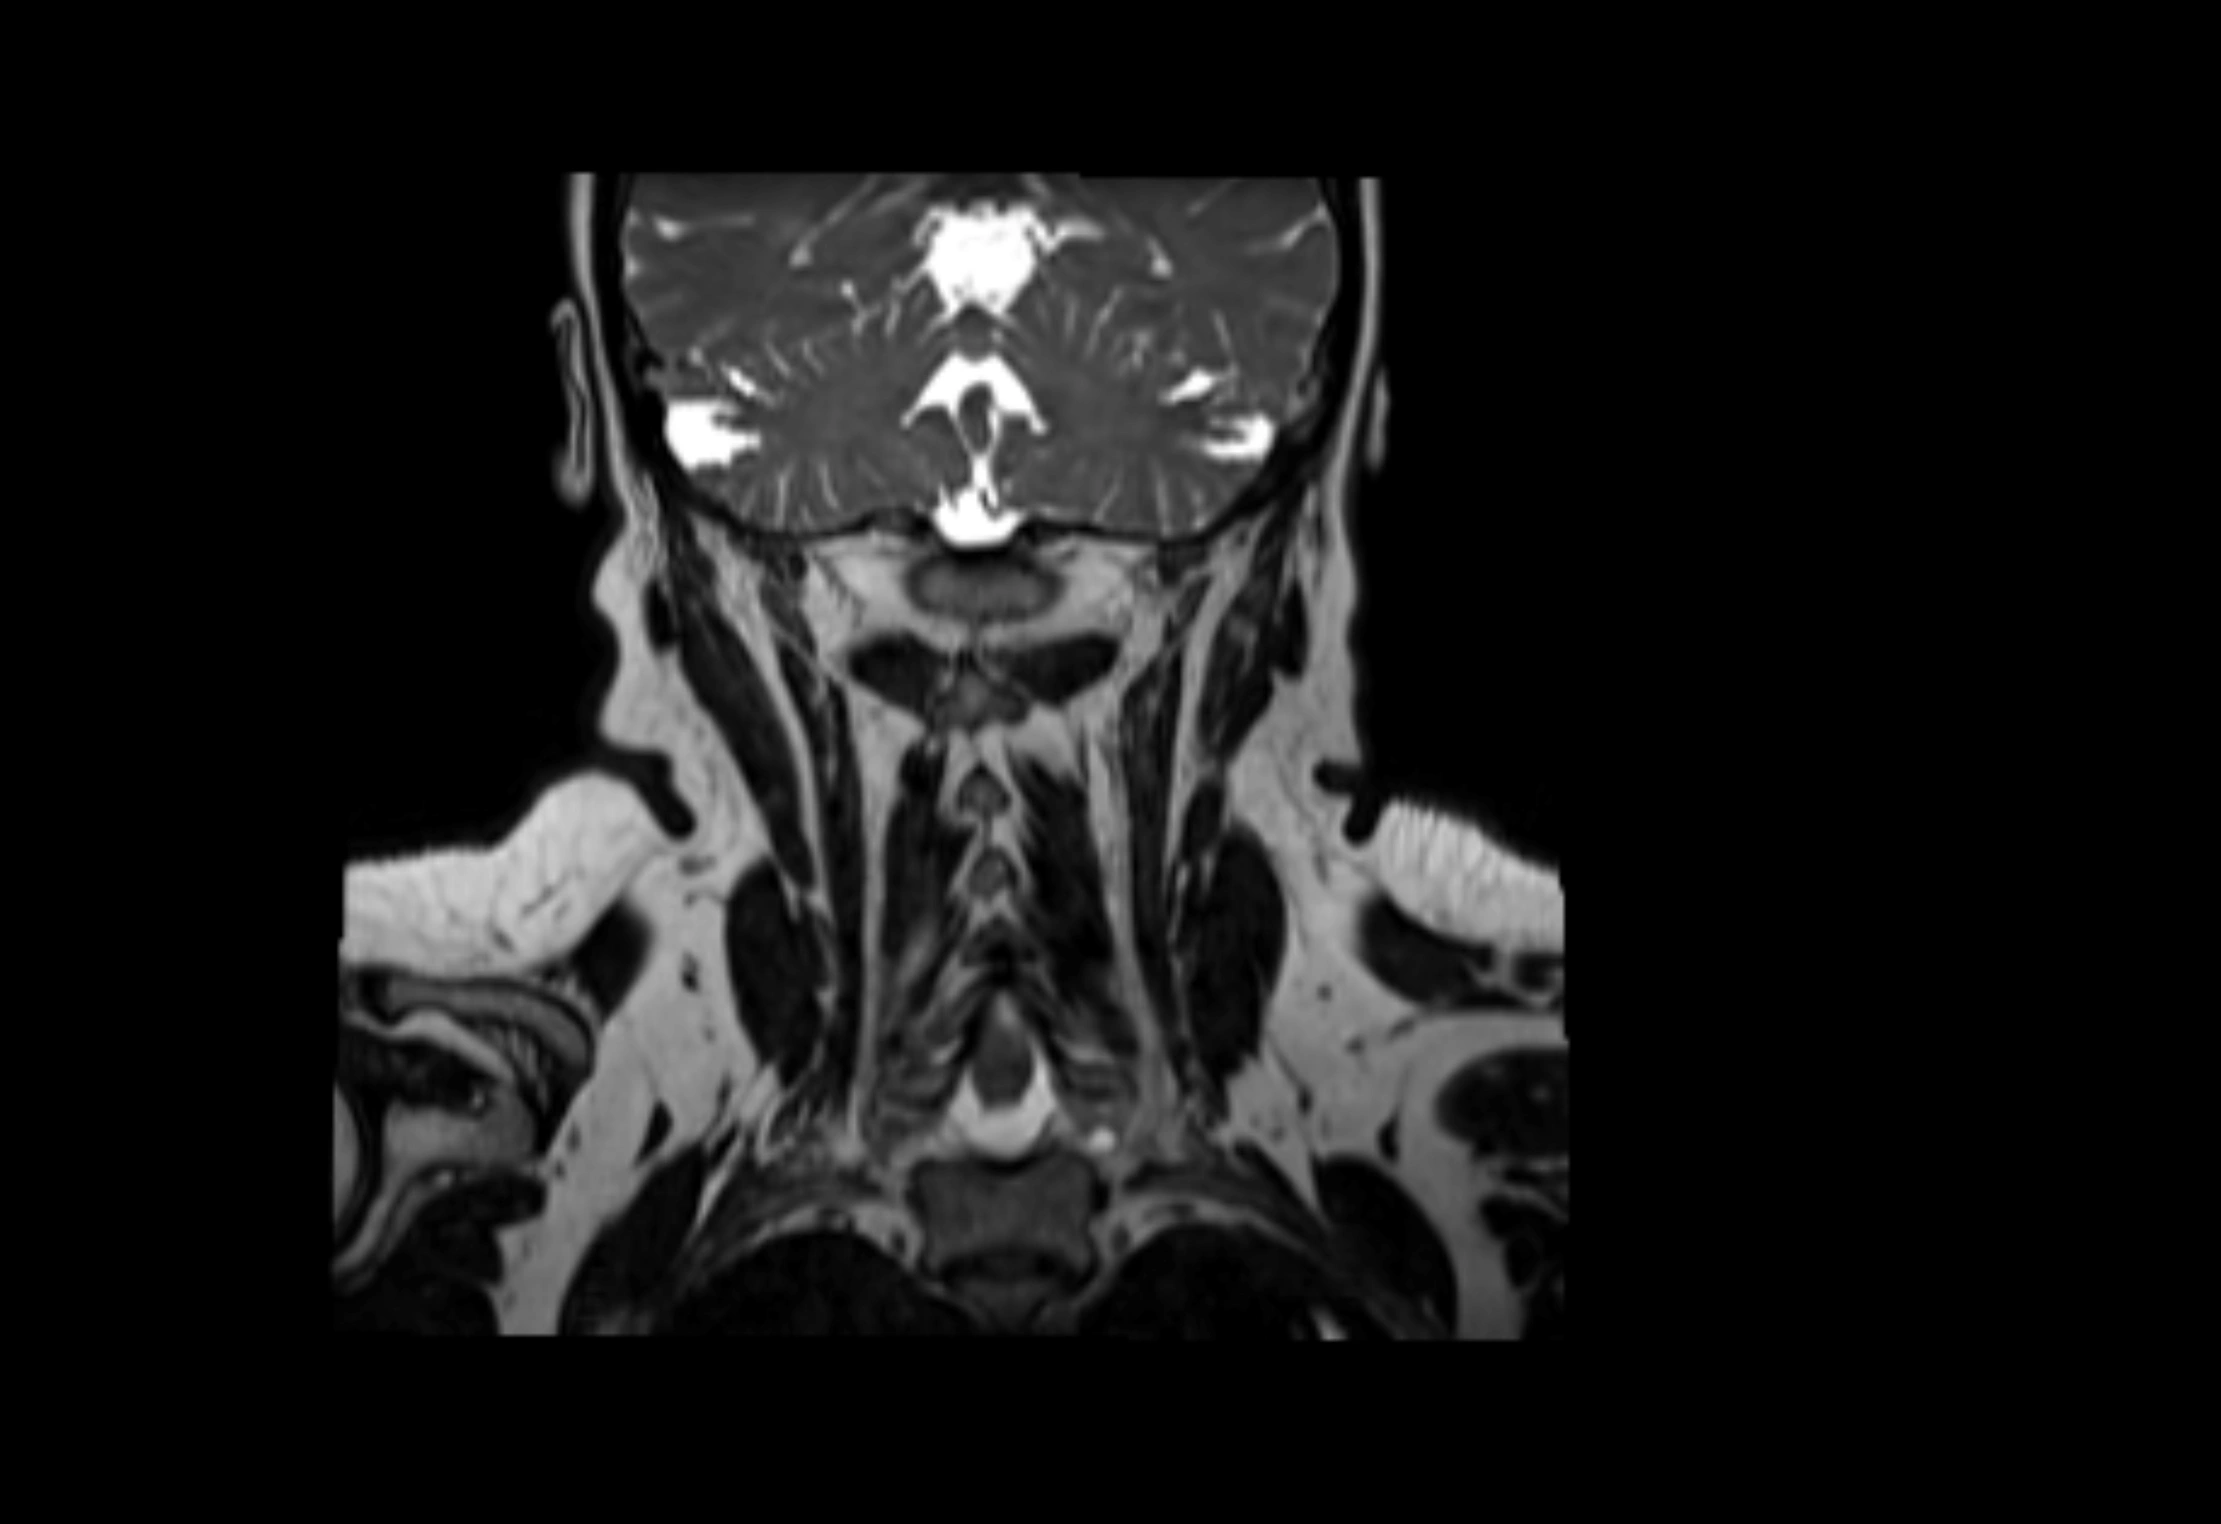

Location

• Found along primary lymph node chains, including preauricular, submandibular, parotid, and occipital regions

• Embedded in subcutaneous fat or superficial fascia, often lateral or posterior to primary nodes

T2-weighted images:

• Nodes show intermediate signal, with surrounding fat bright

• Useful for detecting edema, inflammation, or infiltration

• Fatty hilum may appear slightly hyperintense relative to cortex